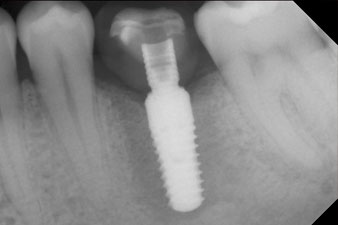

The torque used for the machine-driven placement was 43 Ncm. In addition, after screwing a measuring post (SmartPeg) specially matched to the implant, the ISQ value was measured with the probe of the W&H Osstell ISQ module.

This module is an optional extra for the W&H Implantmed and is docked to the implantology motor (see Fig. 11). The dimensionless ISQ value immediately after insertion was 64 orovestibular and 68 mesiodistal (maximum value = 100).

These values could have indicated open healing or even immediate restoration. Due to the insufficient crestal bone volume at the implant, the region was augmented with the bone chips collected during preparation of the implant bed and sutured to exclude saliva.

The final pictures show the screw-retained monolithic composite crown in place and the x-ray check (Fig. 9 and 10) (6).